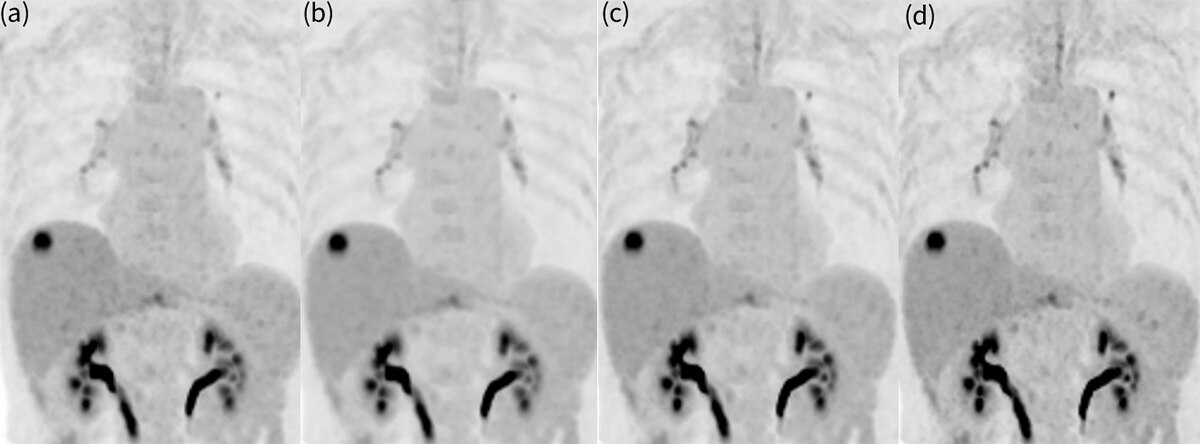

図4. Q.ClearとPrecision DLのMIP画像比較(β500)大腸癌肝転移症例

(a)Q.Clear (b)LPDL (c)MPDL (d)HPDL